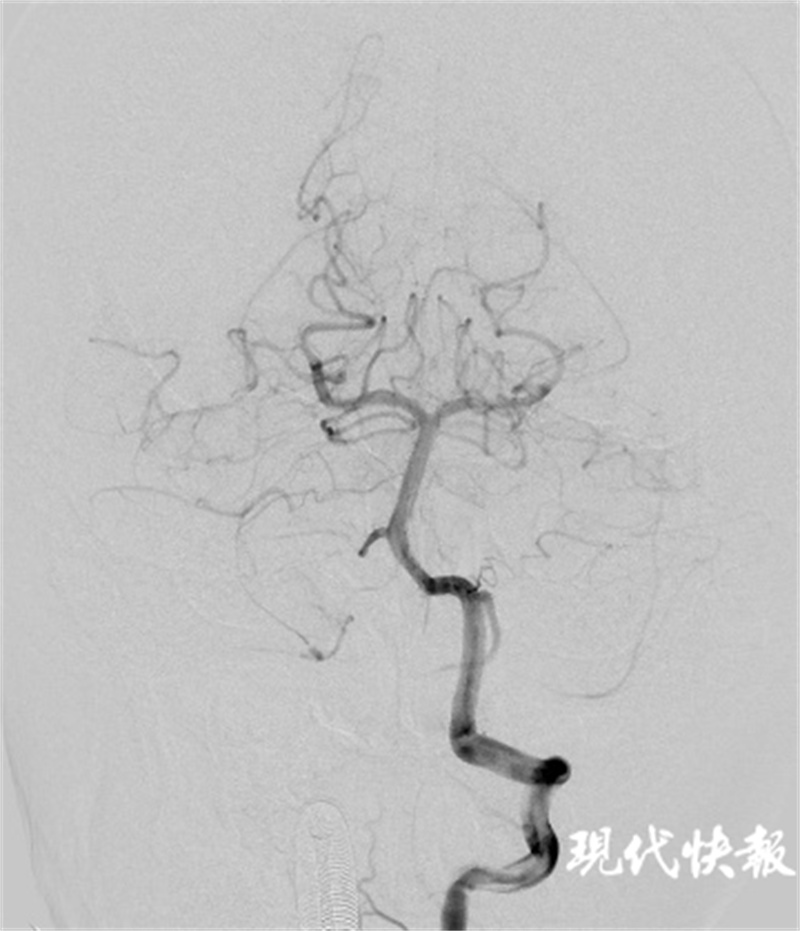

△双侧椎动脉V4段及基底动脉血流恢复通畅

术中造影确认为双侧椎动脉V4段汇合处栓塞。随后引入神经微导管、微导丝及取栓支架,行机械取栓,取出较大血栓块。造影证实血管恢复血流通畅,取栓成功,手术顺利结束。